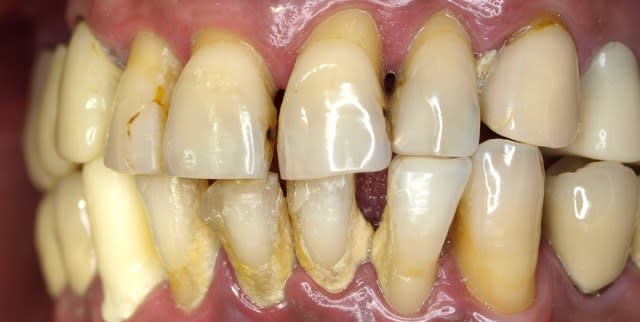

ha ben tiens voila les photo de l'epoque ou je l'ai connu . entre temps il s'est barré voir un aute cd un peu implanto mais pas trop qui lui a viré tout le haut ...